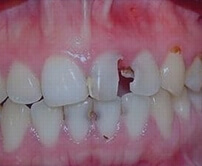

• Exposed pulp pain from a broken tooth.

Broken Crown & Root

Explore how pulpitis and periapical periodontitis develop

Root canal is the best treatment for pulpitis and periapical periodontitis